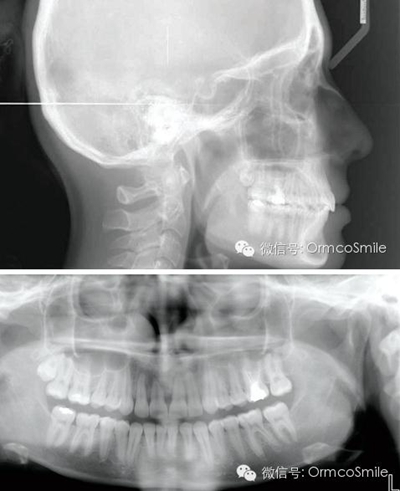

整個(gè)治療時(shí)間為22個(gè)月,制作上頜Hawley保持器和下頜3-3舌側(cè)絲保持。

經(jīng)測(cè)量,上頜第一磨牙遠(yuǎn)中移動(dòng)3.5mm,達(dá)到磨牙Ⅰ類關(guān)系,同時(shí)壓低2mm,而第一前磨牙和上頜切牙沒有明顯的移動(dòng)。上頜第一前磨牙有3°的輕度前傾,這可能是由于上頜只植入了1顆螺紋釘?shù)脑?,作者分析采用兩顆螺紋釘可以減少這種副作用。在上頜磨牙遠(yuǎn)中移動(dòng)過程中,下頜平面角減少了1°,且其持續(xù)到正畸治療結(jié)束。上頜牙弓寬度有輕度擴(kuò)大。